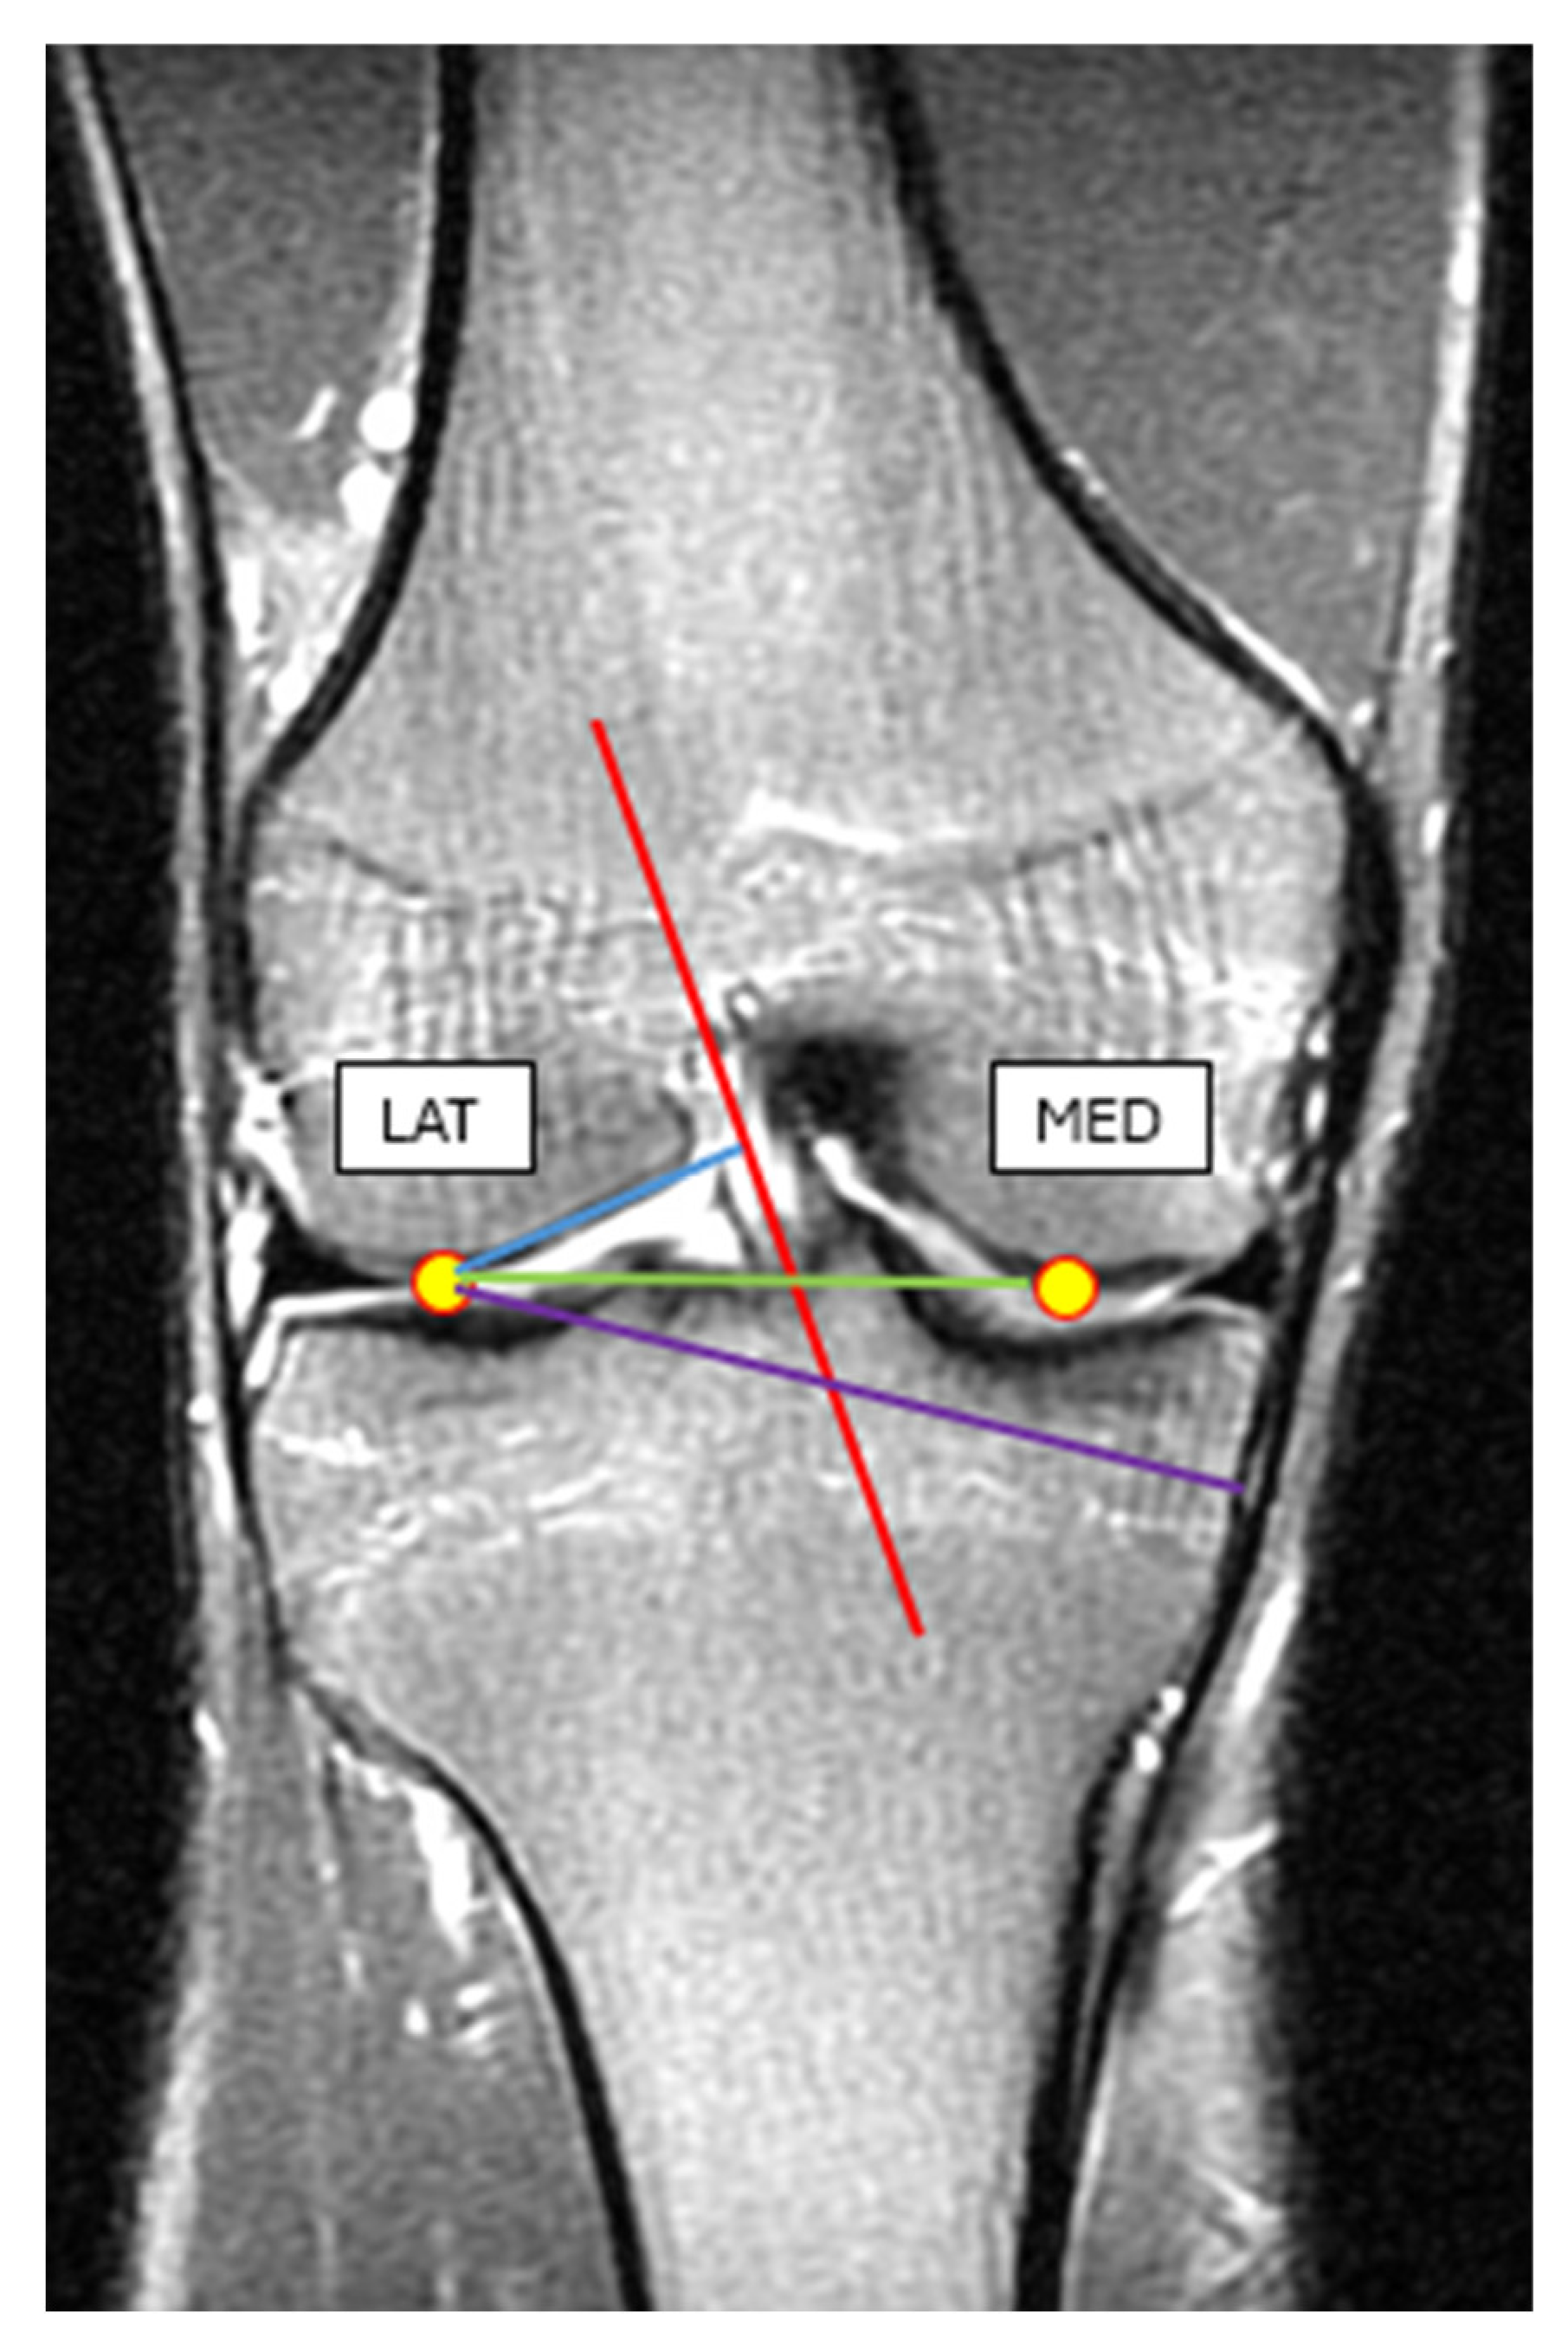

To reach our goal, we have also collected MRI images and anthropometric data of 15 healthy male individuals with more than 10 years of organized sports background (age = 19–23 years, body height = 188.5 ± 8.6 m, body weight = 80.2 ± 6.8 kg). MRI measurements were taken from the individual’s dominant leg. In the MRI images of the knee, we have identified the lateral and the medial condyles and by using the MRI image software (RadiAnt DICOM Viewer 2024.2 version), we measured the lateral condyle–ACL distance, lateral condyle–MCL distance, and lateral condyle–medial condyle distance (Figure 8). For the required anthropometric data, we have measured the ground-lateral condyle and the lateral condyle–greater trochanter distance, respectively (Figure 8, Table 2).

Figure 8. MRI image of the knee in an extended position. Blue line: the lateral condyle–ACL distance, purple line: lateral condyle–MCL distance, green line: lateral condyle–medial condyle distance.